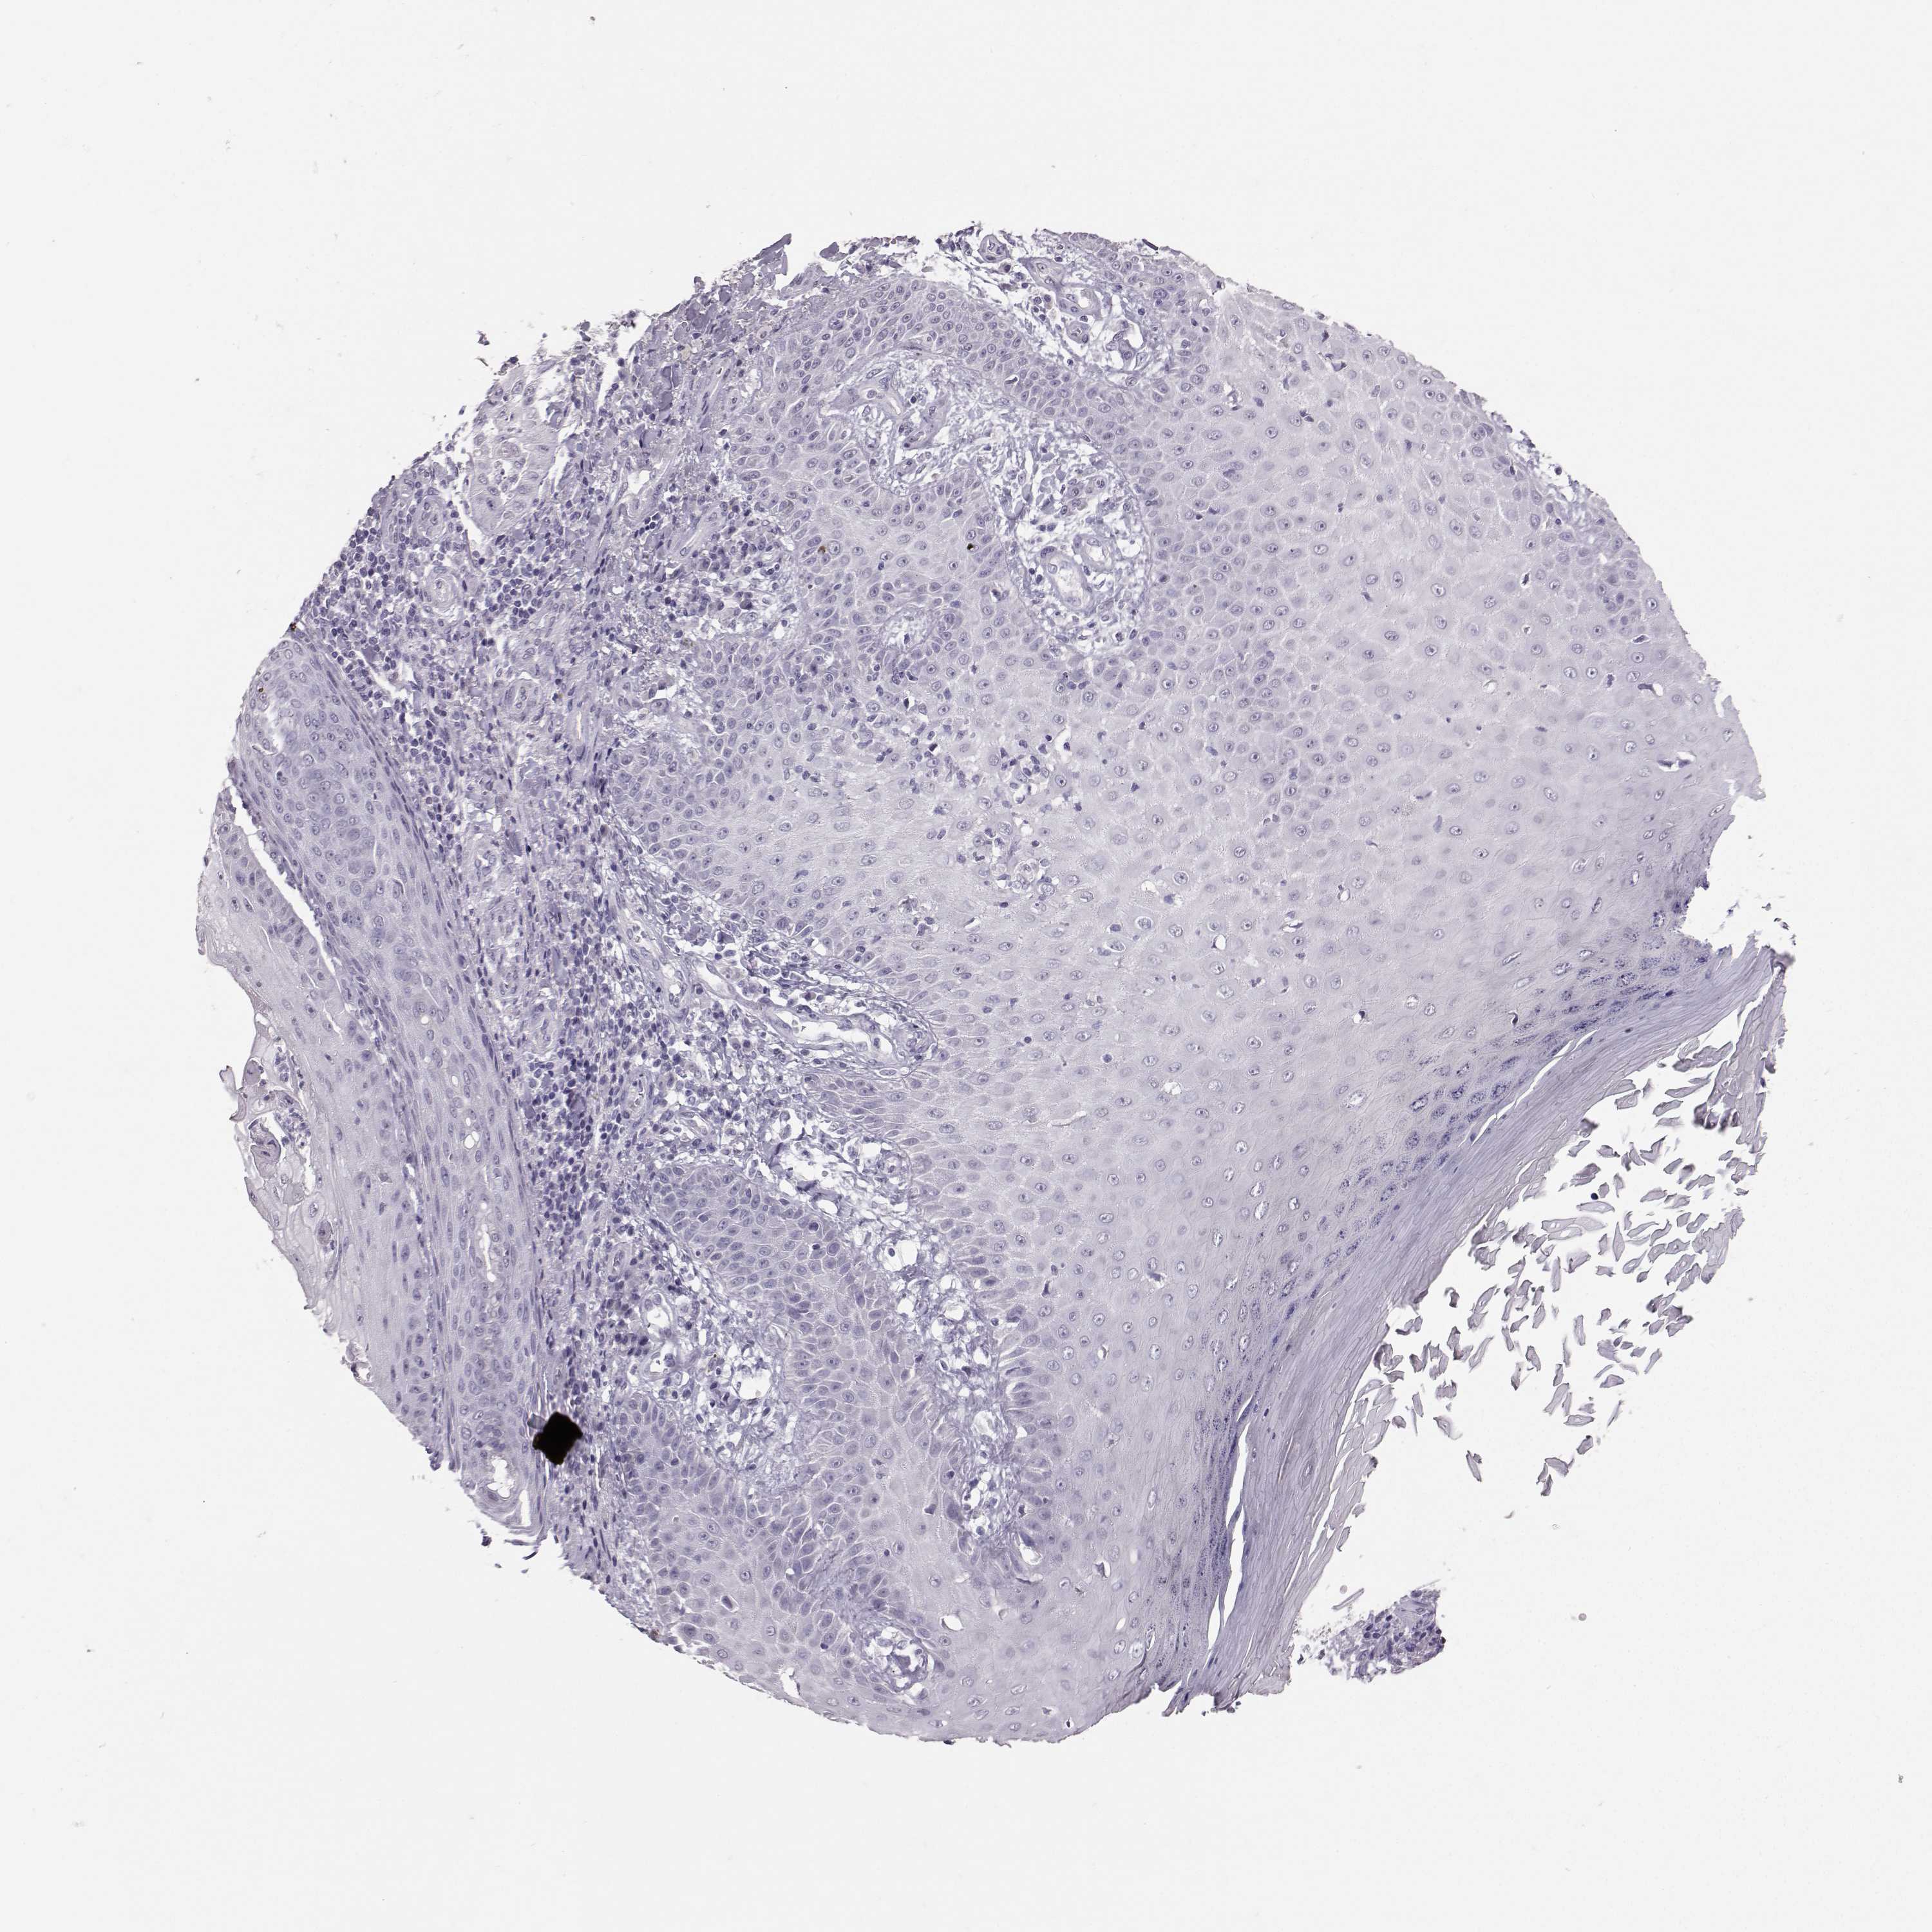

Basal cell and squamous cell cancer

SKIN CANCER - Protein expressioni

A mouse-over function shows sample information and annotation data. Click on an image to view it in a full screen mode. Samples can be filtered based on level of antibody staining by selecting one or several of the following categories: high, medium, low and not detected. The assay and annotation is described here.

Each image is clickable and will lead to virtual microscopy that enables deeper exploration of all samples and also displays staining intensity scores, fraction scores and subcellular localization as well as patient and tissue information for each sample.

Basal cell carcinoma

Adnexal tumor, benign